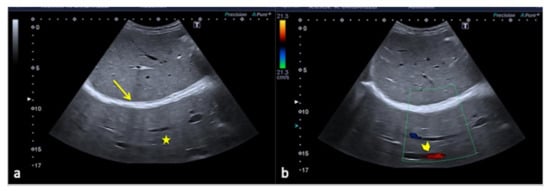

Figure 24. Longitudinal US B-mode (a) and color-Doppler (b) scan of the inguinal canal show a blockage of the inguinal canal misinterpreted as an inguinal hernia with congested intestinal loop. On CT scan (c) it appears to be a right epididymitis with funiculitis.

Figure 25. Rouleaux formation over the venous valves (a, arrows). After distal compression, the blood was squeezed and the rouleaux was finally cleared (b,c).